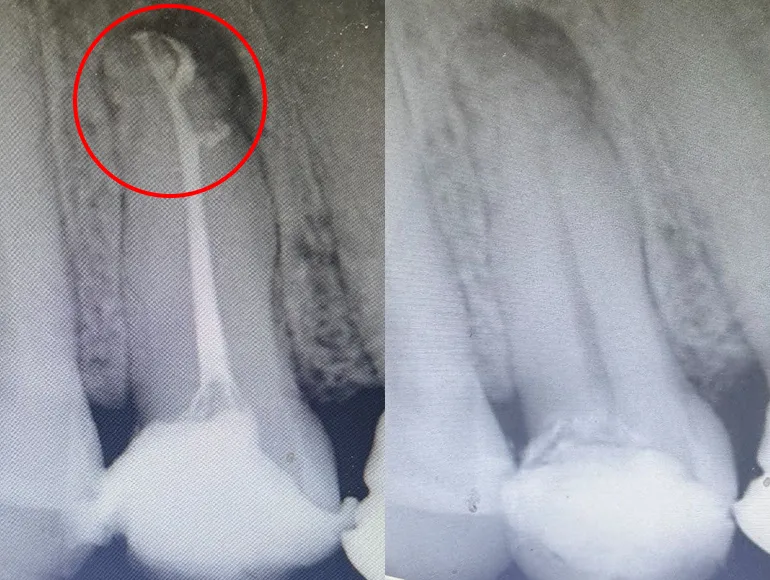

Retreatment of Rootcanal

Case by Dr. Taha Azimaie: Retreatment of failed rootcanal can give a patient another chance to retain the tooth. Retreatment is case selective and not all failed rootcanals are treatable. In this case root canal has failed due to poor sealing of the canals (The white lines in the roots) during the first treatment. Please note the sharp deviation of the canal at the tip of the root (the white line)